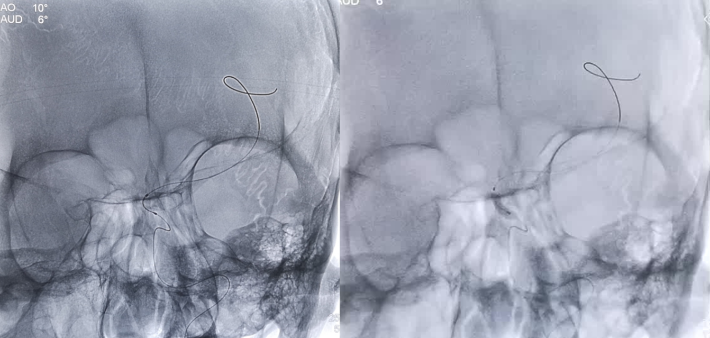

考虑狭窄段为夹层样改变,多角度导引导管造影,以更清晰地区分真假腔,选择最佳工作角度

微导丝通过狭窄血管段

放置微导丝远端至左侧大脑中动脉上干M2段